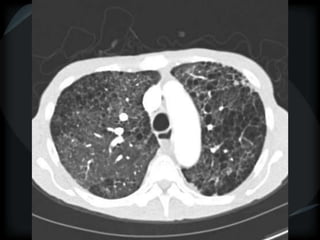

Airspace Patterns

 Diffuse ground-glass

 Patchy consolidation (peripheral)

 Inter and intralobular septal thickening / ground glass/crazy paving

 Reverse halo/atoll sign

 Hogshead cheese sign

 Perilobular pattern

 Organising pneumonia – COP/BOOP

 Chronic eosinophilic pneumonia

 Alveolar proteinosis

 Desquamative interstitial pneumonitis

 Alveolar microlithiasis

 Alveolar sarcoid

 BAC

Airspace Patterns  Diffuseground-glass  Patchy consolidation (peripheral)  Inter and intralobular septal thickening / ground glass/crazy paving  Reverse halo/atoll sign  Hogshead cheese sign  Perilobular pattern  Organising pneumonia – COP/BOOP  Chronic eosinophilic pneumonia  Alveolar proteinosis  Desquamative interstitial pneumonitis  Alveolar microlithiasis  Alveolar sarcoid  BAC